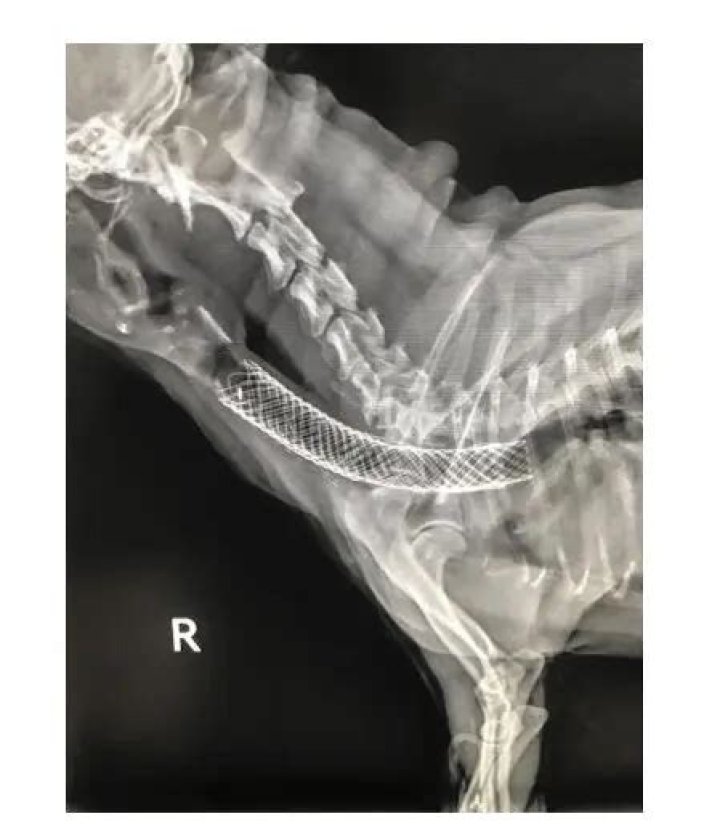

Collapsing Trachea in dogs. Three tips from Dr. Dan!